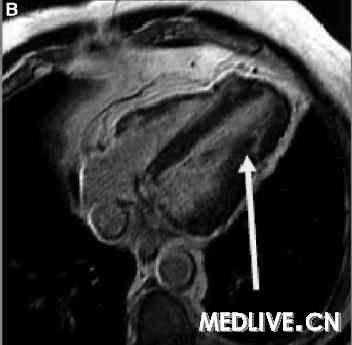

我们用一个带6个元件相控阵列线圈的1.5T的MRI扫描器。通过使用一种稳态梯度回波技术获取标准视图的电影回放,实施标准的心室功能检查。在心脏轴位和短轴平面用屏住呼吸的T1加权快速自旋回波MRI检查心脏和心包形态,并且在静脉给予钆对比剂后10分钟获取对比增强图像。MRI显示心尖处的心包缺如以及双心室尖部疝(图2和3),这些发现引导我们(将该患者)诊断为部分性CAP,LAD中部远端狭窄通过心包环来解释。用MRI完全确定CAP,用心室尖部疝解释LAD受压,以及已被证明的缺血导致了外科干预(图4A和4B)。在左乳内动脉成功地实施了心包成形术联合LAD旁路。术后即时MRI显示与心包成形术相关的心尖部运动明显改善。对照冠状动脉造影显示左乳内动脉通透性良好,LAD变形部分消失(图5)。该患者经过1年随访后目前没有(发生不良)事件。

图2. 心脏轴位T1 MRI显示左心包的部分性缺损 |

图3B. MRI显示双心室尖部疝 |